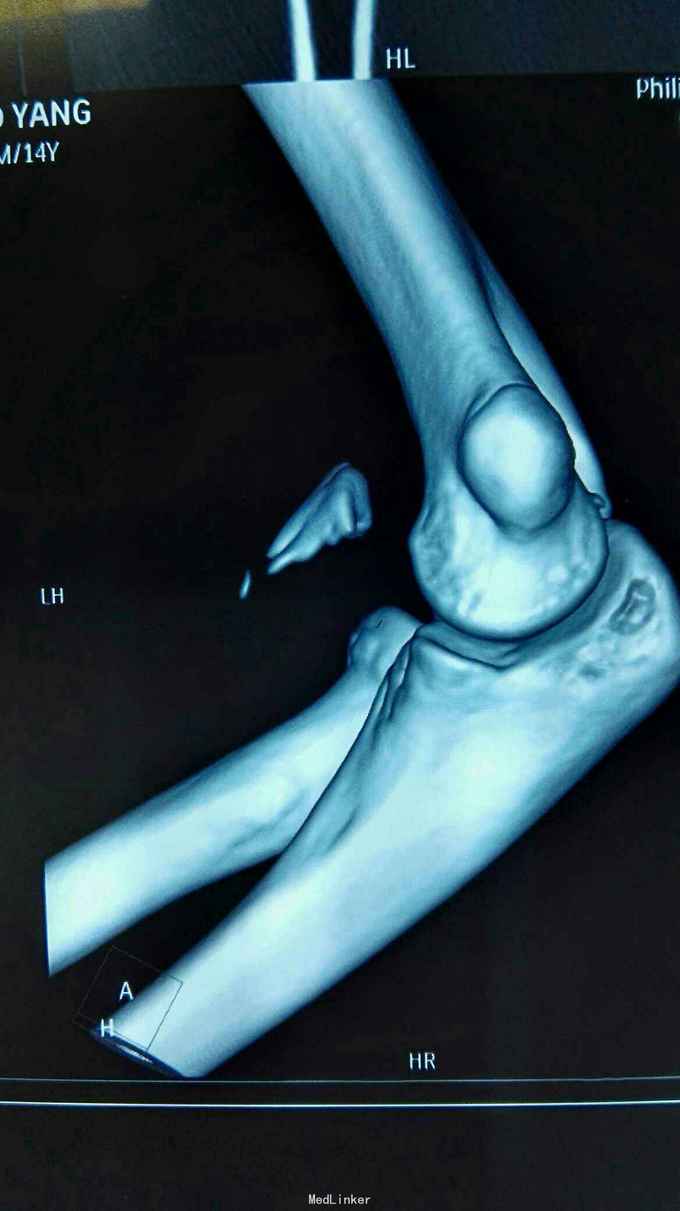

右肘跌伤疼痛伴不能活动1天。 患者,男,14岁,1天前跌倒,感右肘部剧痛,不能活动,急送当地医院拍片示:右肘关节脱位,尺骨冠狀突骨折,右桡骨小头骨折,行手法复位,今来我院就诊。

查体:右肘关节高度肿胀,触痛,活动功能障碍手指末端感觉血运正常。 辅查:x线,CT:右肘关节脱位,右尺骨冠突骨折,右桡骨小头骨折

诊断:右肘恐怖三联症。 治疗:伤后第6天在全麻下行右肘恐怖三联症切开复位内固定术,术中先取肘外侧弧形切口,显露桡骨头,用2枚埋头螺钉固定桡骨头,见右肘外侧副韧带尺侧束断裂,用锚钉固定外侧副韧带。取右肘内侧弧形口,显露冠状突,见冠状突骨折块很小,移位较远,复位,2枚螺钉固定,内侧副韧带前束断裂,修补,术后石膏因定。